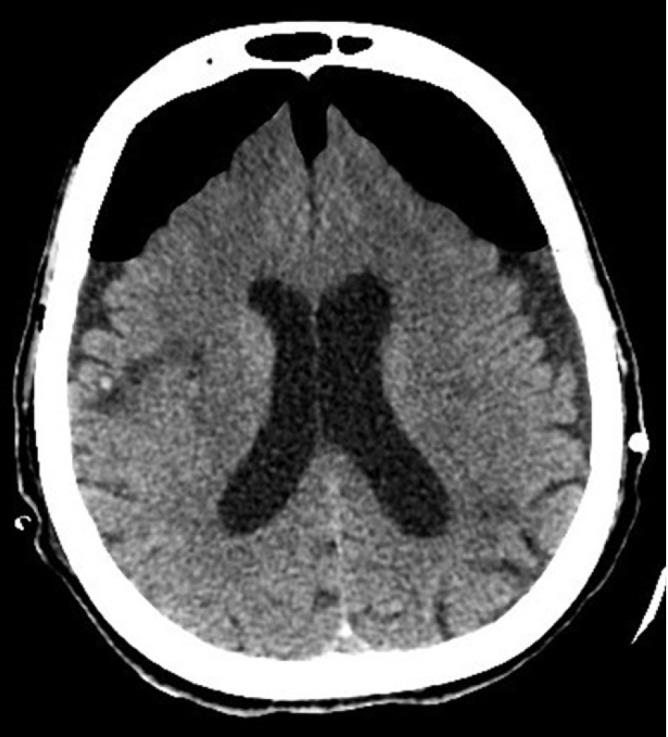

Collection of air in the cranial cavity is called pneumocephalus. Although simple pneumocephalus is a benign condition, accompanying increased intracranial pressure can produce a life-threatening condition comparable to tension pneumothorax, which is termed tension pneumocephalus. We report a case of tension pneumocephalus after drainage of a cerebrospinal fluid hygroma. The tension pneumocephalus was treated with decompression craniotomy, but the patient later died due to the complications related to critical care. Traumatic brain injury and neurosurgical intervention are the most common causes of pneumocephalus. Pneumocephalus and tension pneumocephalus are neurosurgical emergencies, and anesthetics and intensive care management like the use of nitrous oxide during anesthesia and positive pressure ventilation have important implications in their development and progress. Clinically, patients can present with various nonspecific neurological manifestations that are indistinguishable from a those of a primary neurological condition. If the diagnosis is questionable, patients should be investigated using computed tomography of the brain. Immediate neurosurgical consultation with decompression is the treatment of choice.

颅腔内积气称为气颅。虽然单纯气颅是一种良性情况,但伴随的颅内压升高可产生与张力性气胸类似的危及生命的情况,即张力性气颅。我们报告一例脑脊液囊肿引流后发生张力性气颅的病例。该张力性气颅采用颅骨减压术治疗,但患者后来因重症监护相关并发症死亡。创伤性脑损伤和神经外科干预是气颅最常见的原因。气颅和张力性气颅是神经外科急症,麻醉和重症监护管理(如麻醉期间使用氧化亚氮和正压通气)对其发生和发展具有重要影响。临床上,患者可出现各种非特异性神经表现,与原发性神经疾病难以区分。如果诊断存疑,应使用脑部计算机断层扫描对患者进行检查。立即进行神经外科会诊并减压是首选治疗方法。